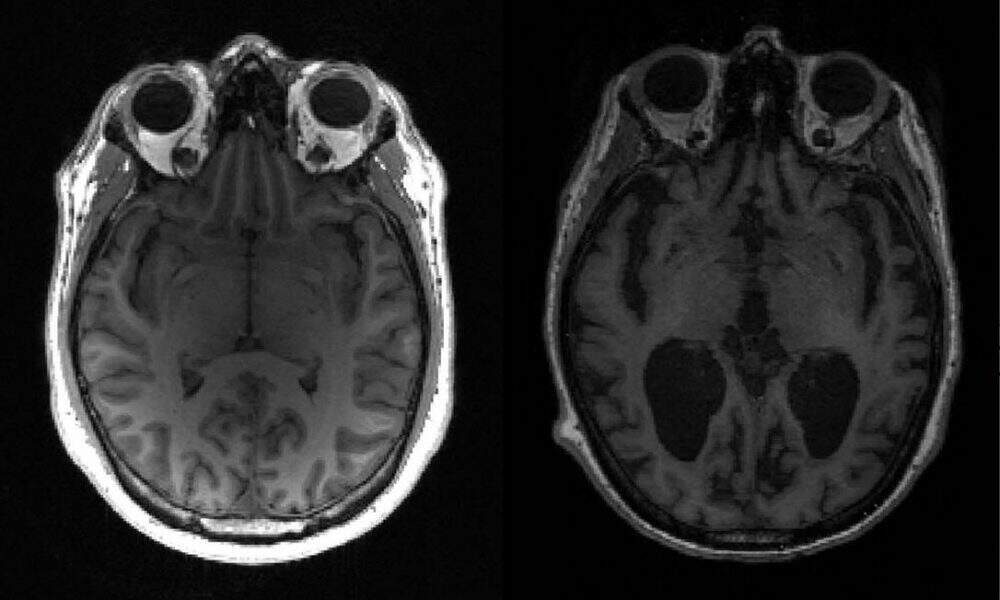

A empresa está desenvolvendo um imunizante para o Alzheimer que visa combater os oligômeros beta-amiloide – que são cadeias de proteínas que quando se acumulam no cérebro provocam as manifestações clínicas da doença. O imunizante estimula a produção de anticorpos que podem reconhecer as formas beta-amiloide capazes de desenvolver neurotoxinas.